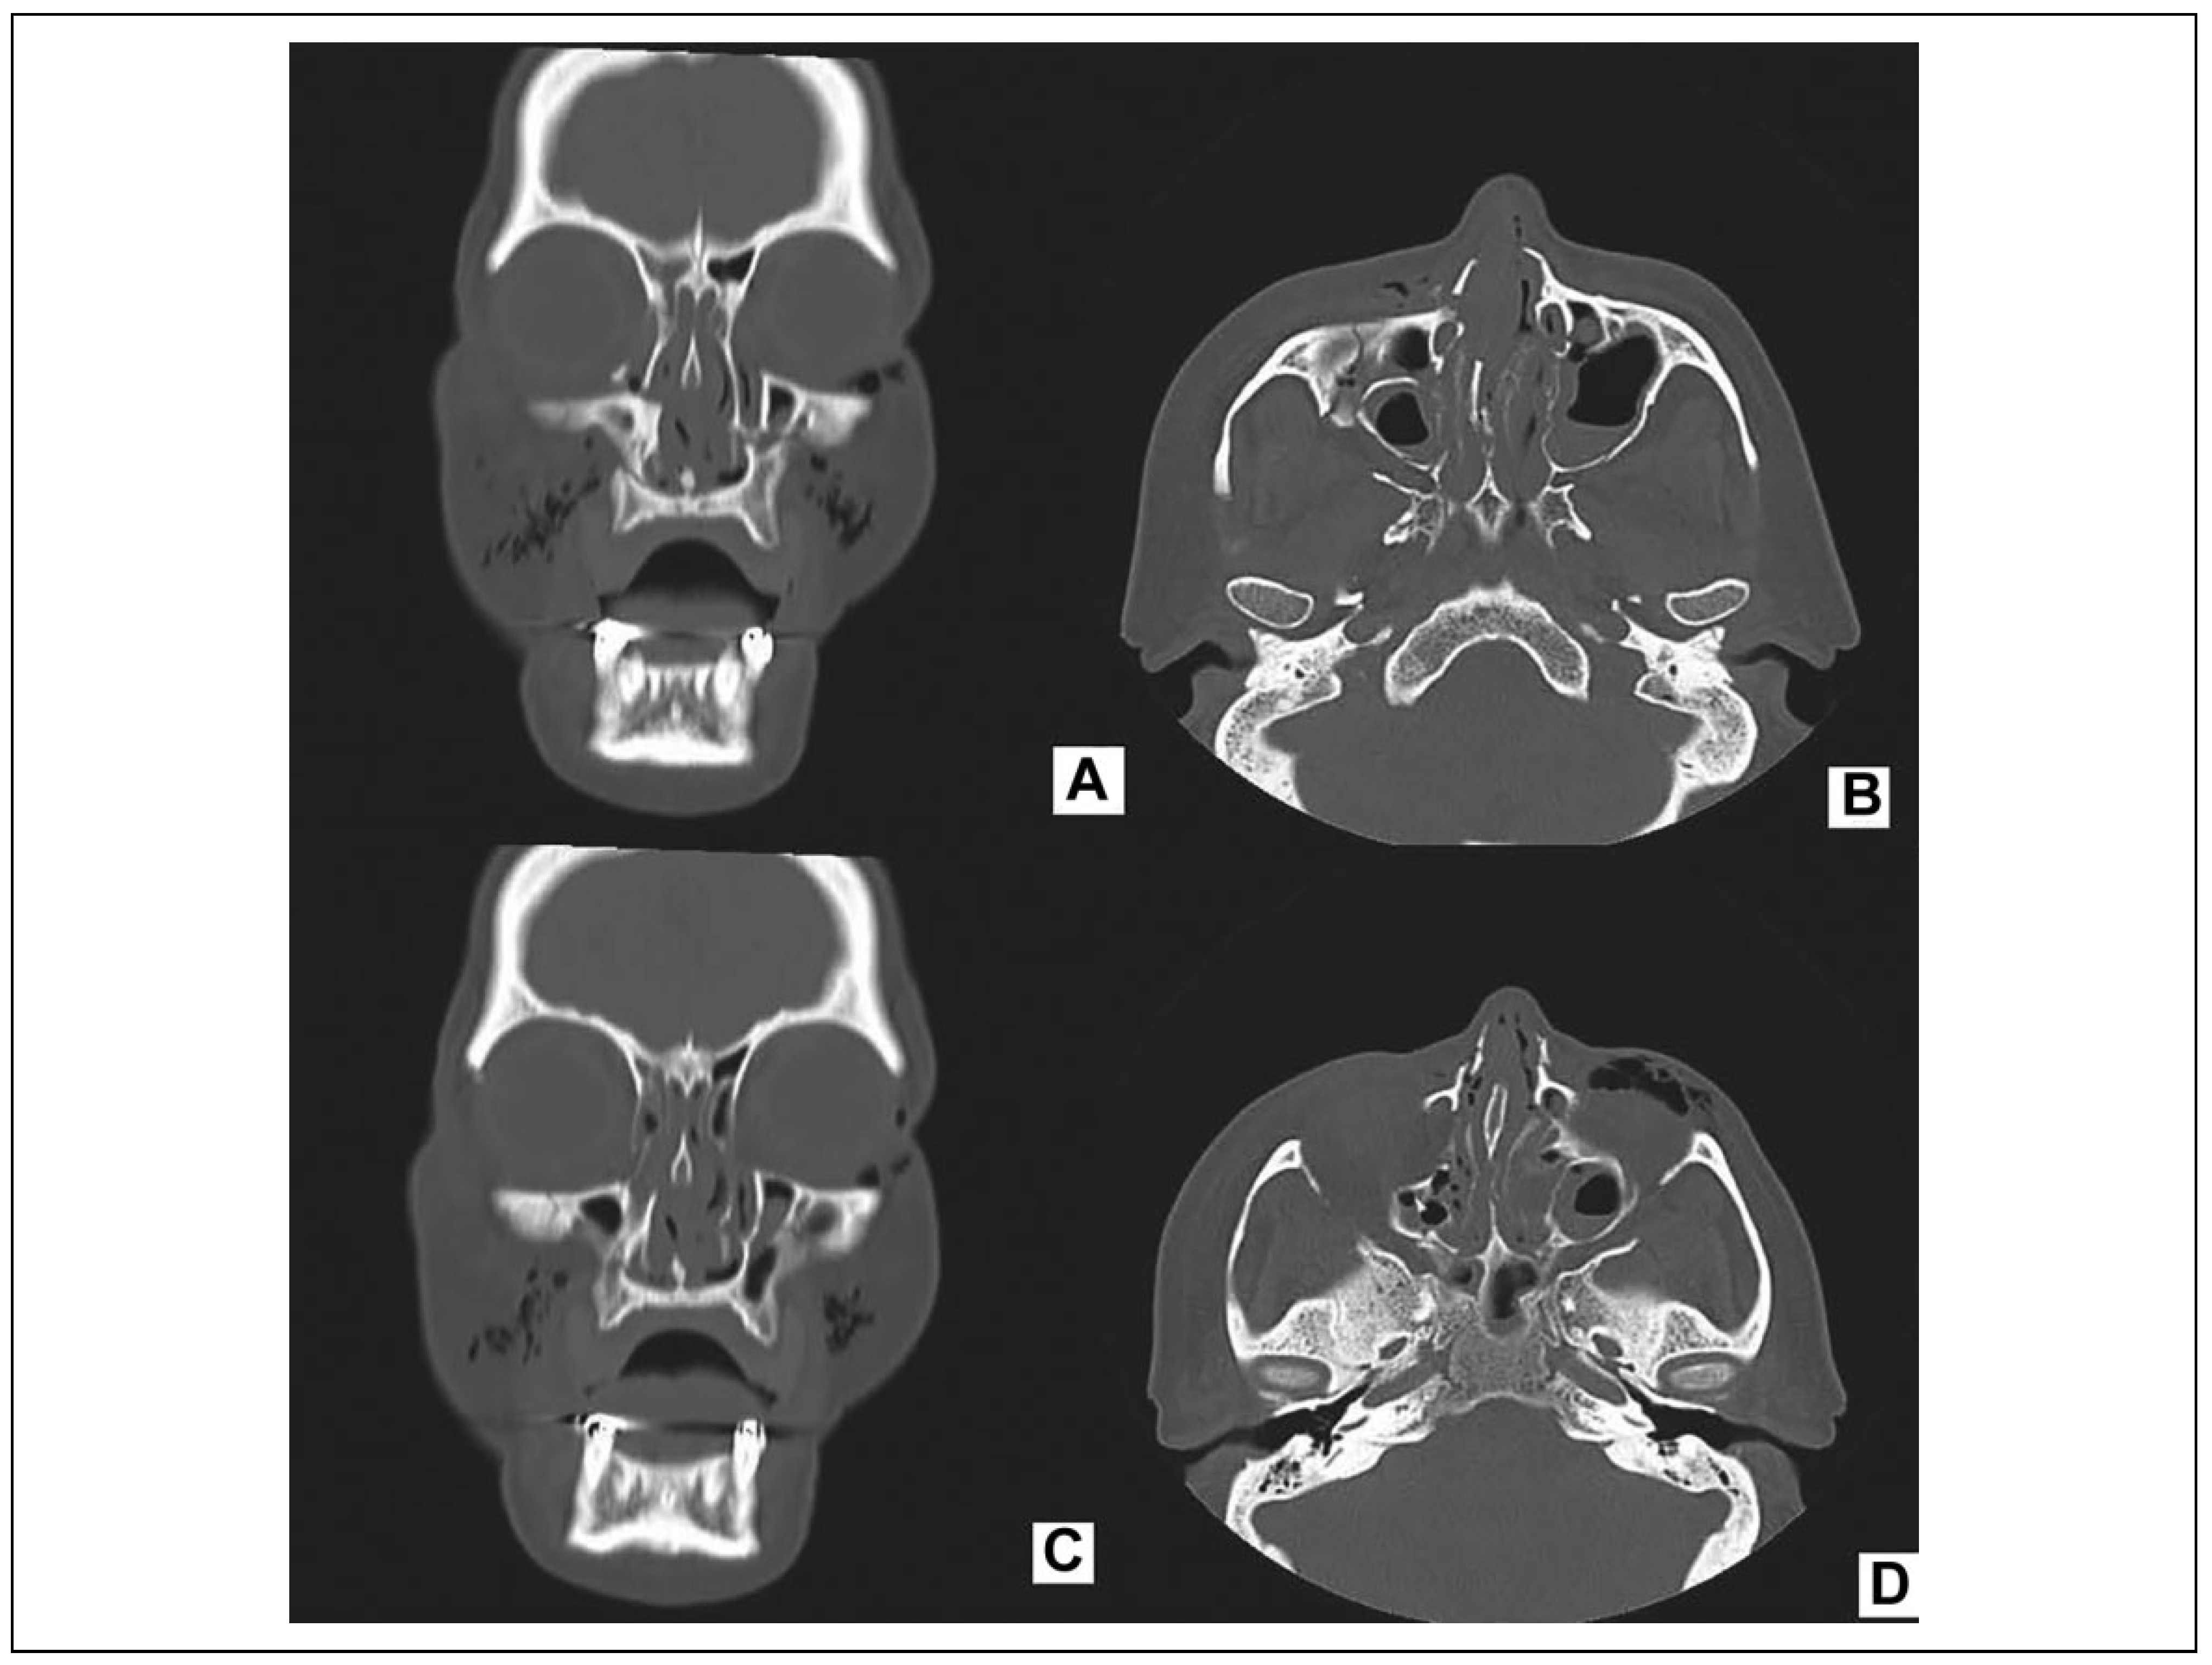

A study performed by Leles et al[22] found that the highest incidence of facial injuries involves the nasal cavity, followed by the zygomatic complex and the orbital region. Arasarena et al[23] also report that, in cases of physical aggression against women, nasal fractures are the most common injuries. The current findings corroborate this study, since isolated nasal fracture was most prevalent among the patients included herein (21 patients; 39.1%). This major nasal fracture prevalence is a different pattern when compared with the other types of etiologies, which we have shown in this study, such as falls and traffic accident. In those cases, the zygomatic orbital complex fracture was more frequent, with 68% and 65.7%, respectively; however, all trauma cases can be associated with nasal fracture. This frequency may be explained by the position of the nose on the face and its greater exposure to trauma. A study in 2011 reported that the high incidence of nasal fractures is likely the result of the relatively low amount of force required to fracture this relatively thin bone of the face.[24] Exactly, what was seen in this current study, physical aggression, is generally considered to be a lower energy trauma; thus, the possibility of zygomatic trauma is smaller in this case (Figure 3). Low-energy trauma should rely on meticulous clinical examination, affecting the extension of imaging, type of intubation, and future surgical approaches. High-energy trauma requires total body CT.[25]

Figure 3. Pattern of facial fracture considering the energy: A and B, coronal and axial section—the etiology was fall: medium energy, zygomatic and nasal fracture. C and D, coronal and axial section—the etiology was physical aggression, isolated nasal fracture.